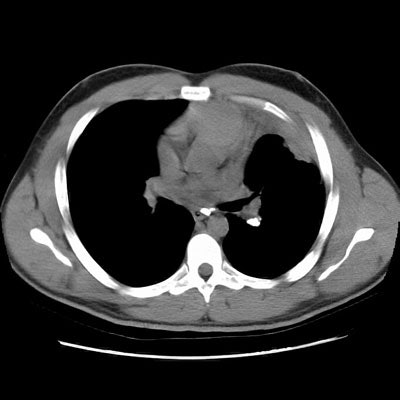

Rounded atelectasis in a patient with prior granulomatous infection

Asbestos related pleural disease is not the only cause of rounded atelectasis. The patient shown in the images below had a prior granulomatous infection with densely calcified left hilar adenopathy. There is extensive plerual thickening seen along the left anterior pleural surface. Rounded consolidated lung can be seen to abut this area of pleural thickening. Lung markings "swirl" into the area of abnormality. There is shift of the mediastinal structures to the left consistent with volume loss.